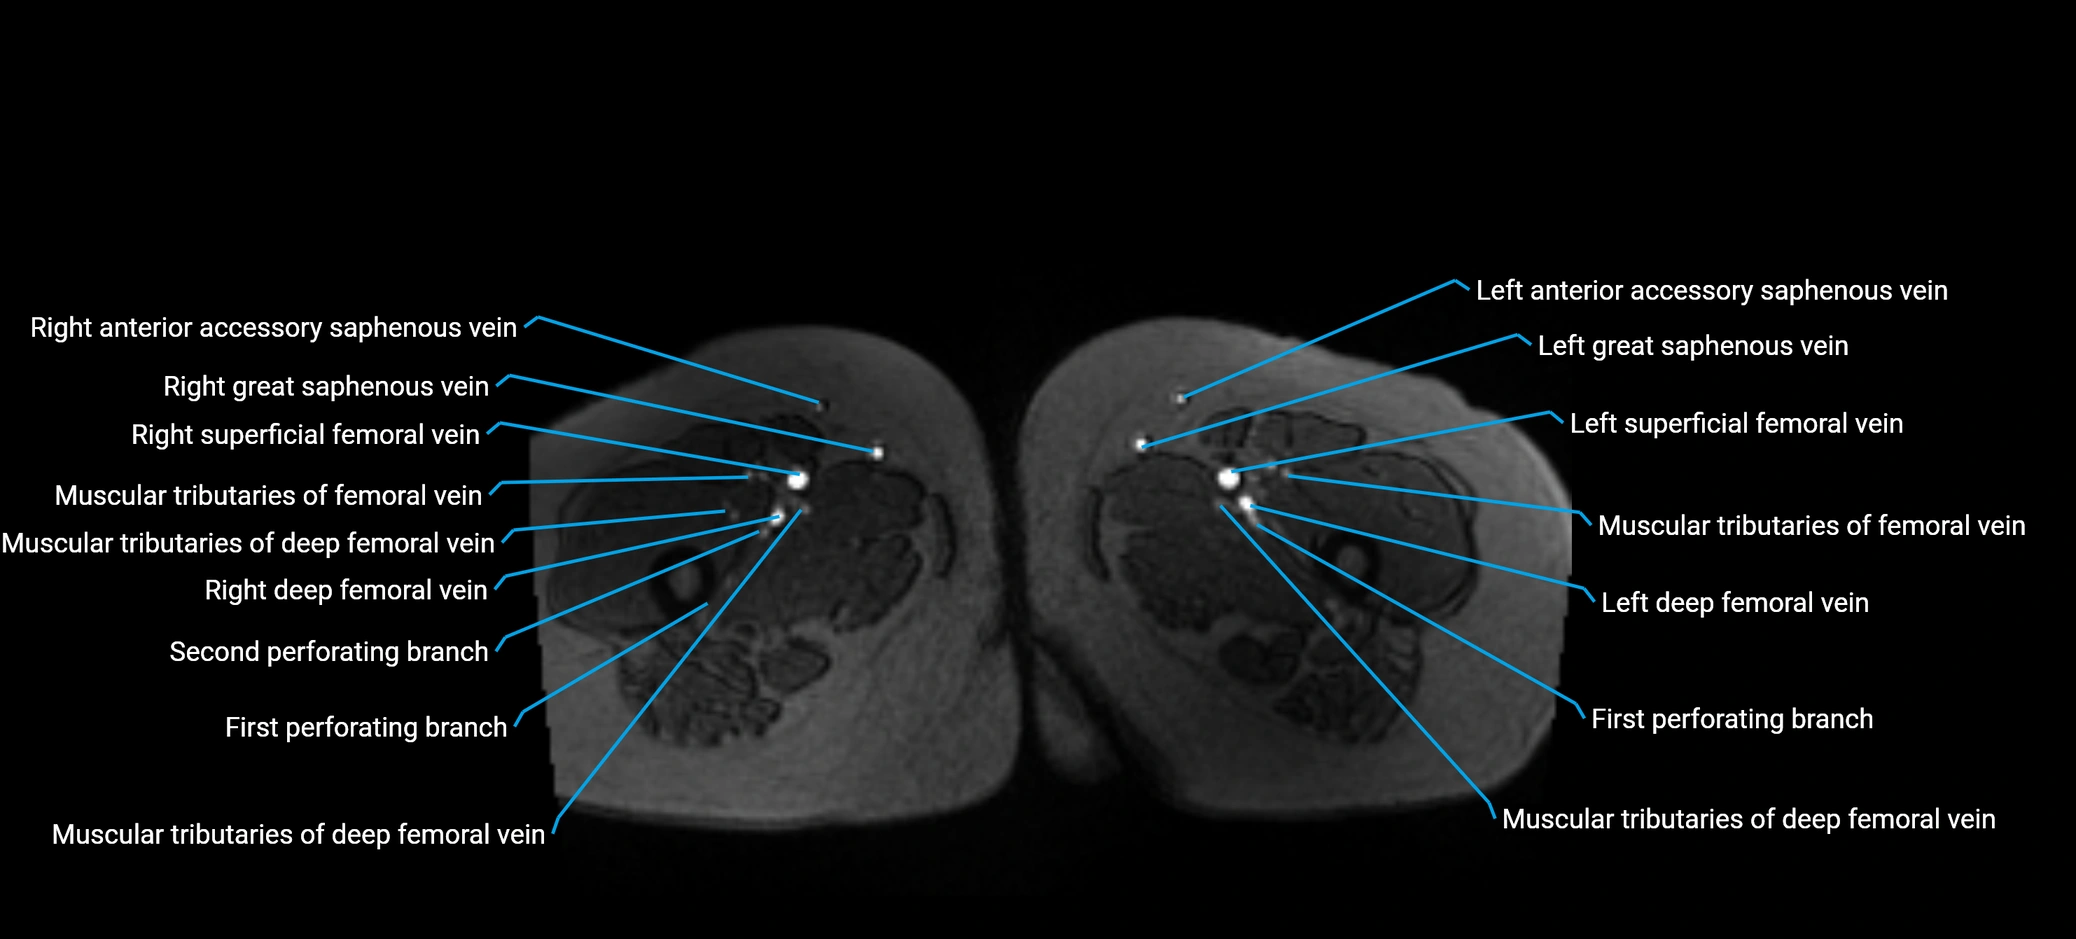

MRI image

image